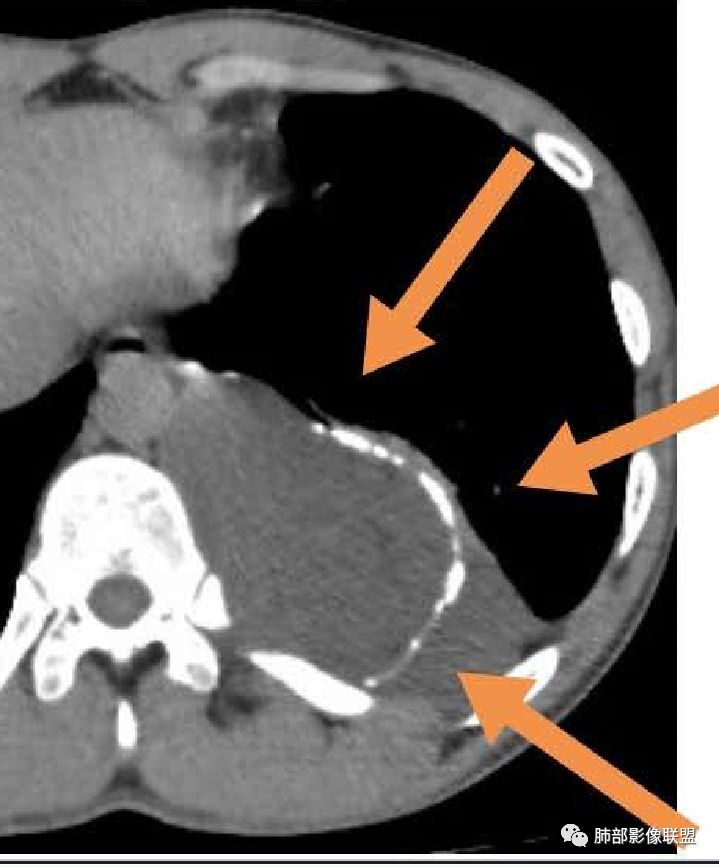

首先需要定位在哪?纵隔?胸壁?

应该是跨区域了。跨区域一般我们的分析:

1、病灶由一侧突入到另外一侧。

2、两个区域病灶融合,这一例好像符合后者。

现在我们重新回顾性分析这个病例的影像特点:

1.含有少量脂肪密度成分,位于病灶中央区,应当是病灶内的一部分,或者说至少这部分不是被包绕卷入的。常见病灶内含有脂肪组织的肿瘤:多种脂肪瘤、脂肪肉瘤、畸胎瘤、其他肿瘤伴脂肪化生或分化。

2.病灶中间弧形稍高密度影,提示纤维组织可能,而且很有张力并呈分叶状,伴弧形钙化,提示这个倾向于病灶的包膜。